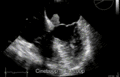

Echocardiogram of atrial myxoma -

Echocardiogram showing atrial myxoma[9]

-